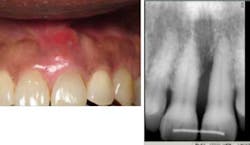

Case No. 2 — Miss Novice

A 12-year-old African American female presented for treatment of localized rapidly progressive periodontitis on No. 19 and No. 30 prior to orthodontic treatment. Prior dental care included prophys and sealants. The LANAP protocol was performed at one appointment with local anesthetic.

Miss Novice before the LANAP protocol.

Miss Novice showed radiographic evidence of bone regeneration seven months post LANAP. She completed orthodontics and shows stable bone three years post LANAP.

Miss Novice after the LANAP protocol.